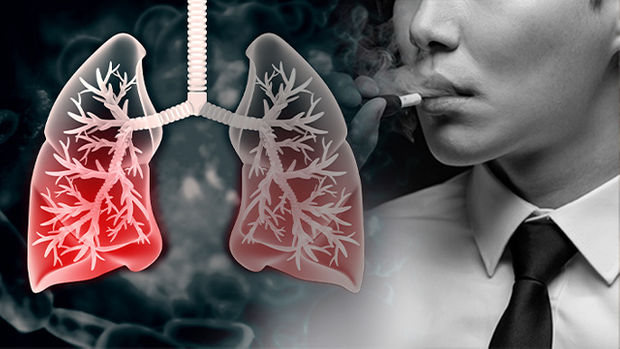

흡연자와 비흡연자를 비교하면 흡연자는 폐암에 걸릴 확률이 낮게는 15배, 높게는 80배까지 높아질 수 있고, 폐암의 마지막 원인 중 하나이기 때문에 흡연자라면 금연을 하는 것이 정말 좋습니다.

또한 흡연의 경우 간접흡연으로 인해 주변 비흡연자에게도 영향을 미칠 수 있으므로 주의해야 합니다. 담배를 피우지 않는다면 야채와 과일을 충분히 섭취하는 것이 좋습니다. 신선할수록 좋으며, 이는 영양소를 섭취하고 시간이 지남에 따라 면역 체계를 구축할 수 있는 좋은 방법입니다.